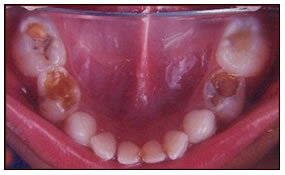

Pulpotomy ,Pulpectomy & SS Crown

All severely damaged milk teeth are saved by this procedure wherein the decayed living tissue is removed and filled with restorative material.

The teeth that are saved by this method is further strengthened by capping with metal crowns.